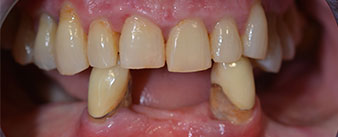

La paziente, 64 anni, presenta una dentatura residua di denti 38, 33 e 43 e una protesi combinata innestata nella mandibola (Fig. 1 e 2).

dentatura residua

Fig. 1

Fig. 2